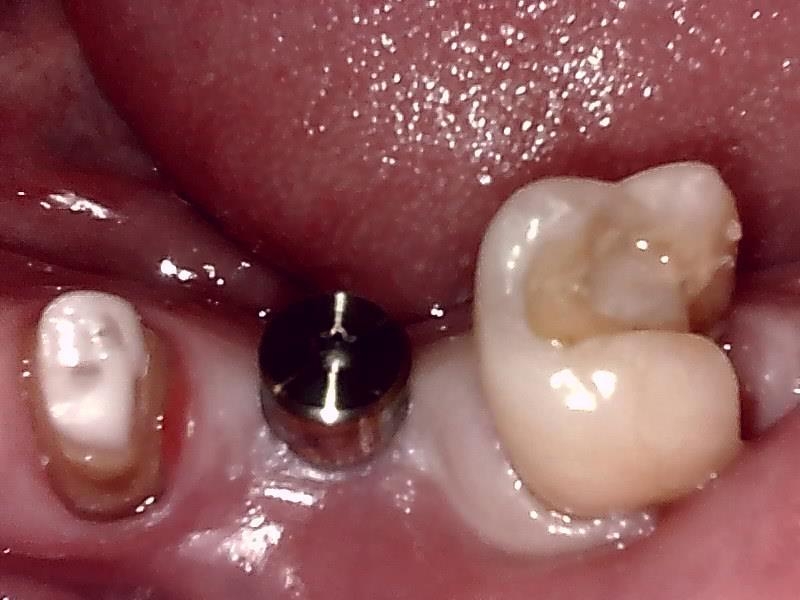

アバットメント装着 (左下)

(ジルコニアアバットメント)